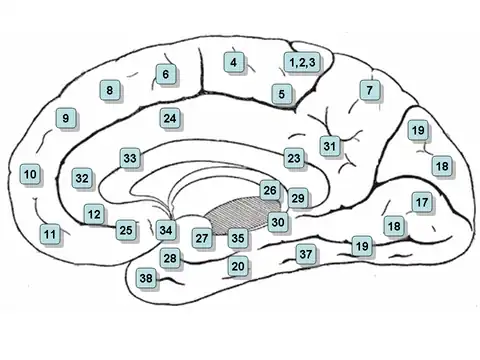

Medial surface of the brain with Brodmann's areas numbered. | |

Brodmann area 26 is the name for a small part of the brain.

In the human this area is called ectosplenial area 26. It is a cytoarchitecturally defined portion of the retrosplenial region of the cerebral cortex. It is a narrow band located in the isthmus of cingulate gyrus adjacent to the fasciolar gyrus internally. It is bounded externally by the granular retrolimbic area 29 (Brodmann-1909).